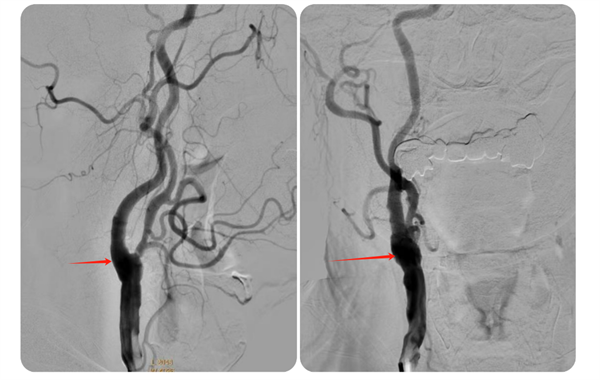

近日,小妲己直播app 神经外科收治了一名74岁高龄且伴有多年高血压、糖尿病史的高危患者何先生(化名)。何先生此前已接受过右侧椎动脉、左侧锁骨下动脉支架植入术,但近期因头晕、左侧肢体乏力等症状再次入院。经过详细检查,医生发现何先生右侧颈内动脉起始部存在重度狭窄,狭窄率高达75%,情况危急。

▲术前脑血管造影

术后,何先生顺利苏醒,回到神经外科病房进行监护治疗,术后7天伤口愈合良好拆线出院。8月何先生来小妲己直播app 复查,DSA检查提示右侧颈动脉狭窄已完全恢复并无再狭窄,头晕及左侧肢体乏力症状也完全缓解了。

▲术后狭窄完全解除